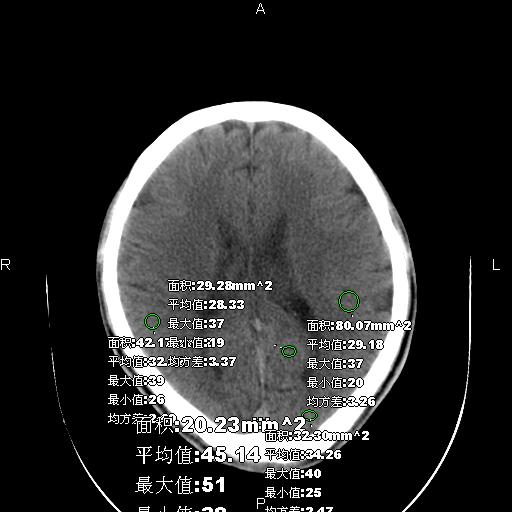

男性,40岁,反复头痛,视物旋转一月余,无呕吐,pe未见明确异常。

我的问题是上矢状窦高密度怎么解释?请各位专家不吝指教,谢谢!

可结合增强或mrv检查除外上矢状窦血栓。